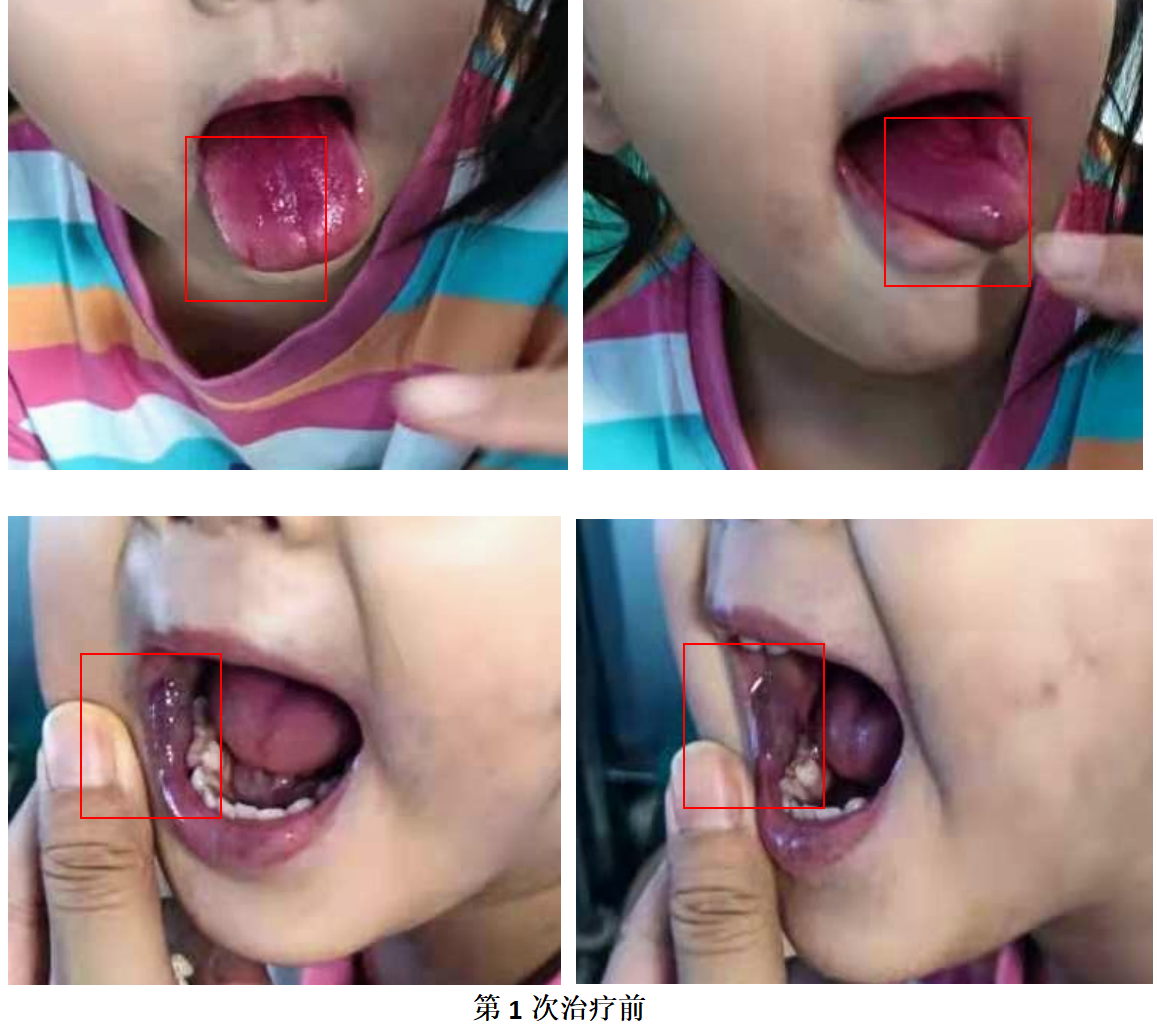

一、初次就诊

2021年5月的一天,申刚主任门诊迎来了一位小患者,患儿家长在3年前发现孩子右口角内侧有紫色包块,明显突出于皮面,哭闹时突出更加明显,右舌部较对侧肿胀,外院曾治疗1次,具体治疗方法不详,无效果。后家长慕名找到申刚主任,申刚主任考虑患儿为典型的静脉畸形,便安排孩子住院进一步介入治疗。

按照手术排期,1个月后,患儿来门诊做好核酸,术前检查后入院,第二天就安排入介入室行介入治疗。孩子全麻下,很顺利的进行了动脉造影、药物灌注、影像引导下硬化治疗等一系列介入手术治疗,术后第一天就平安回家了。因为患儿病灶部位在口腔部且病灶部位相对较大,在确保安全、美观的基础上对患儿进行疗程化治疗。